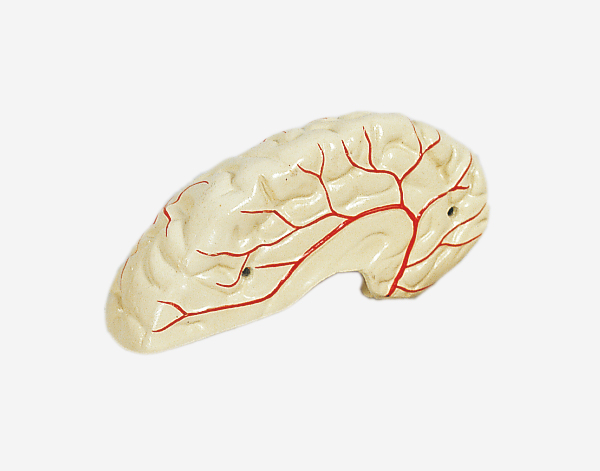

Human Brain With Arteries

Model of Human Brain With Arteries

This model facilitates the medical students to get a correct understanding of the external features of the brain and its arte

rial supply as a whole,as well as the relations between their component portions.External features of the brain:cerebral

hemisphere,brain stem,cerebellum.The arterial supply of the bra inaources,vertebral,internal carotid arteries,arteria supply of the

cerebellum and cerebrum.Made of PVC and can be separated into 7parts,on base.Size(cm):17x17x13